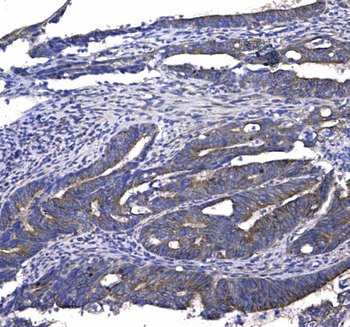

10 μg, 100 μg - Anti-HSD11B2 Antibody [orb316541]

IF, IHC, IHC-Fr, WB

Human, Mouse, Rat

Rabbit

Polyclonal

Unconjugated

10 μg, 100 μg - Anti-CD44 Antibody [orb402179]